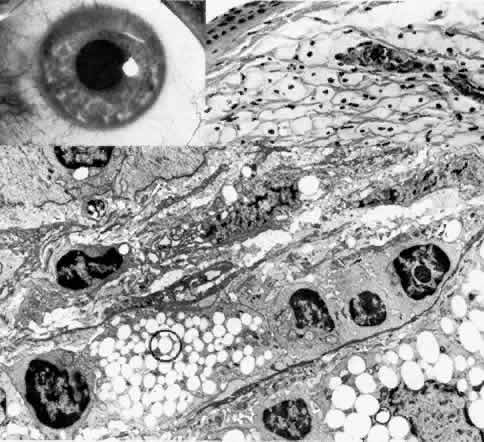

This rare, autosomal dominant dystrophy is detectable very early in life and in some cases is congenital (Fig. 13).161–166 Subtle grayish specks are present in all layers of both corneas, and some appear as rings with relatively less opacified centers. They cause no visual disability. Histopathologic examination has revealed abnormal keratocytes that on transmission electron microscopy show a fibrillogranular substance within intracytoplasmic vacuoles.165 Histochemical staining shows glycosaminoglycans and lipids within these vacuoles.

Fig. 13. Fleck dystrophy (Francois-Neetens). Top left. Artistic representation of discrete, flattened white stromal flecks shows comma, wreath, or dot configuration. Top right. Retroillumination slit lamp photograph demonstrates similar configuration of small, white, granular opacities throughout the stroma. Bottom. Lower right inset is phase-contrast micrograph of a severely affected keratocyte showing foamy cytoplasm with large clear vacuoles (*) and small refractile inclusions (arrowheads) (paraphenylenediamine × 1400). Upper left inset illustrates positive staining for acid mucopolysaccharide limited to a swollen keratocyte (circled) (colloidal iron, × 500). Main figure is transmission electron micrograph of a markedly vacuolated keratocyte filled with fibrillogranular (F) or lipid (L) substances. There are no extracellular abnormalities except an accumulation of the fine granular material (,) and occasional foci of long-spacing collagen (square) (× 12,000). (Nicholson DH, Green WR, Cross HE et al: A clinical and histopathological study of Francois Neetens speckled corneal dystrophy. Am J Ophthalmol 83:554, 1977)